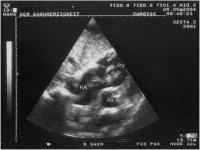

Valvula eustachii

Abbildung 1: Valvula eustachii an der Mündung der V. cava inf. (TTE, subkostaler Längsschnitt)